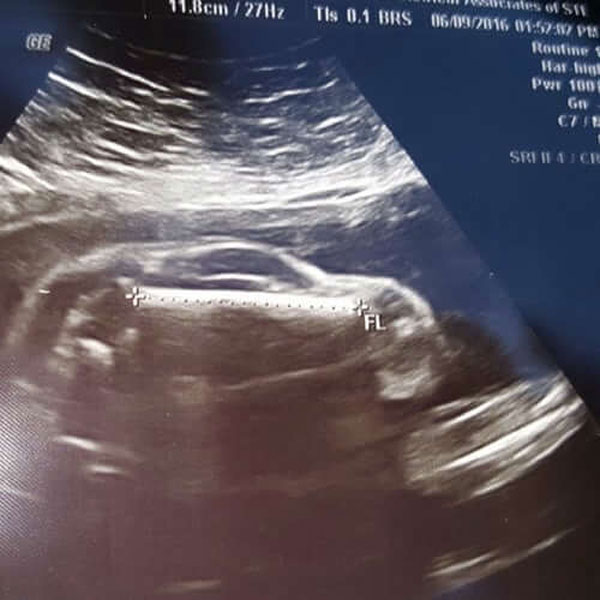

ಅಂತರ್ಜಾಲದಲ್ಲಿ ಒಬ್ಬ ವ್ಯಕ್ತಿಯು ಹೆಮ್ಮೆ ಪಡುತ್ತಾ ತನ್ನ ಹೆಂಡತಿಯು ಒಂದು ಸ್ಪೋರ್ಟ್ಸ್ ಕಾರ್ ಗೆ ಜನ್ಮ ನೀಡಲಿದ್ದಾಳೆ ಎಂದು ಈ ಫೋಟೋವನ್ನು ಹಂಚಿಕೊಂಡಿದ್ದನು. ಈ ಫೋಟೋ ನೋಡಿದ ಮೇಲೆ ನಮಗೂ ಹಾಗೆ ಅನಿಸುತ್ತಿದೆ !